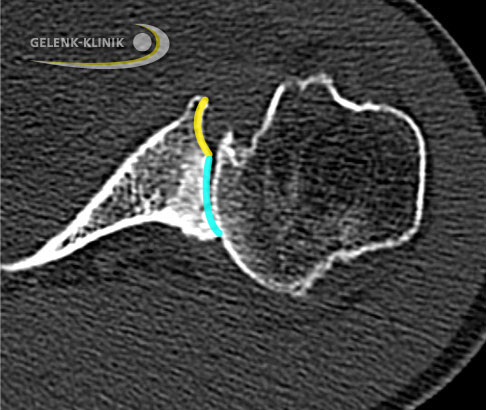

Bestehen Knochendefekte, wie sie bei einem langen Verlauf der Schulterarthrose vor allem im hinteren Bereich der Pfanne (Glenoid) auftreten können, ergänzt der Schulterspezialist die Diagnostik durch eine Computertomographie (CT). Die CT-Technik ermöglicht dem Arzt bei große Knochendefekten eine 3-D-Planung zur optimalen Vorbereitung, wenn er eine Operation in Betracht zieht.

Computertomographie: Wie ist der Knochen beschaffen?

Die Computertomographie (CT) gibt dem Orthopäden Auskunft über die Knochenqualität. Die Qualität der Knochensubstanz ist besonders wichtig, wenn der Arzt die Verankerung von Implantaten zur Behandlung der Omarthrose plant. Vor allem bei älteren Patienten mit einer bereits eingetretenen Cuff-Arthropathie ist die CT-Untersuchung wichtig, um die Knochensubstanz des Gelenkpfanne (Glenoid) zu bewerten.